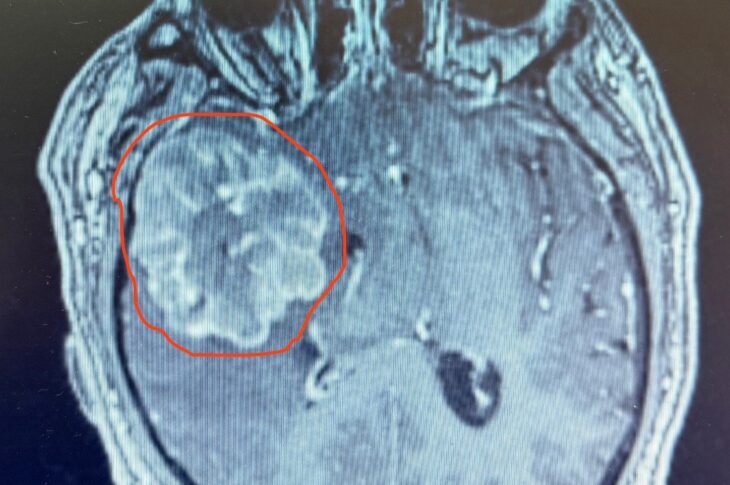

МӘМС істе: 6 сантиметрден асатын ісік

4 августа, 2025